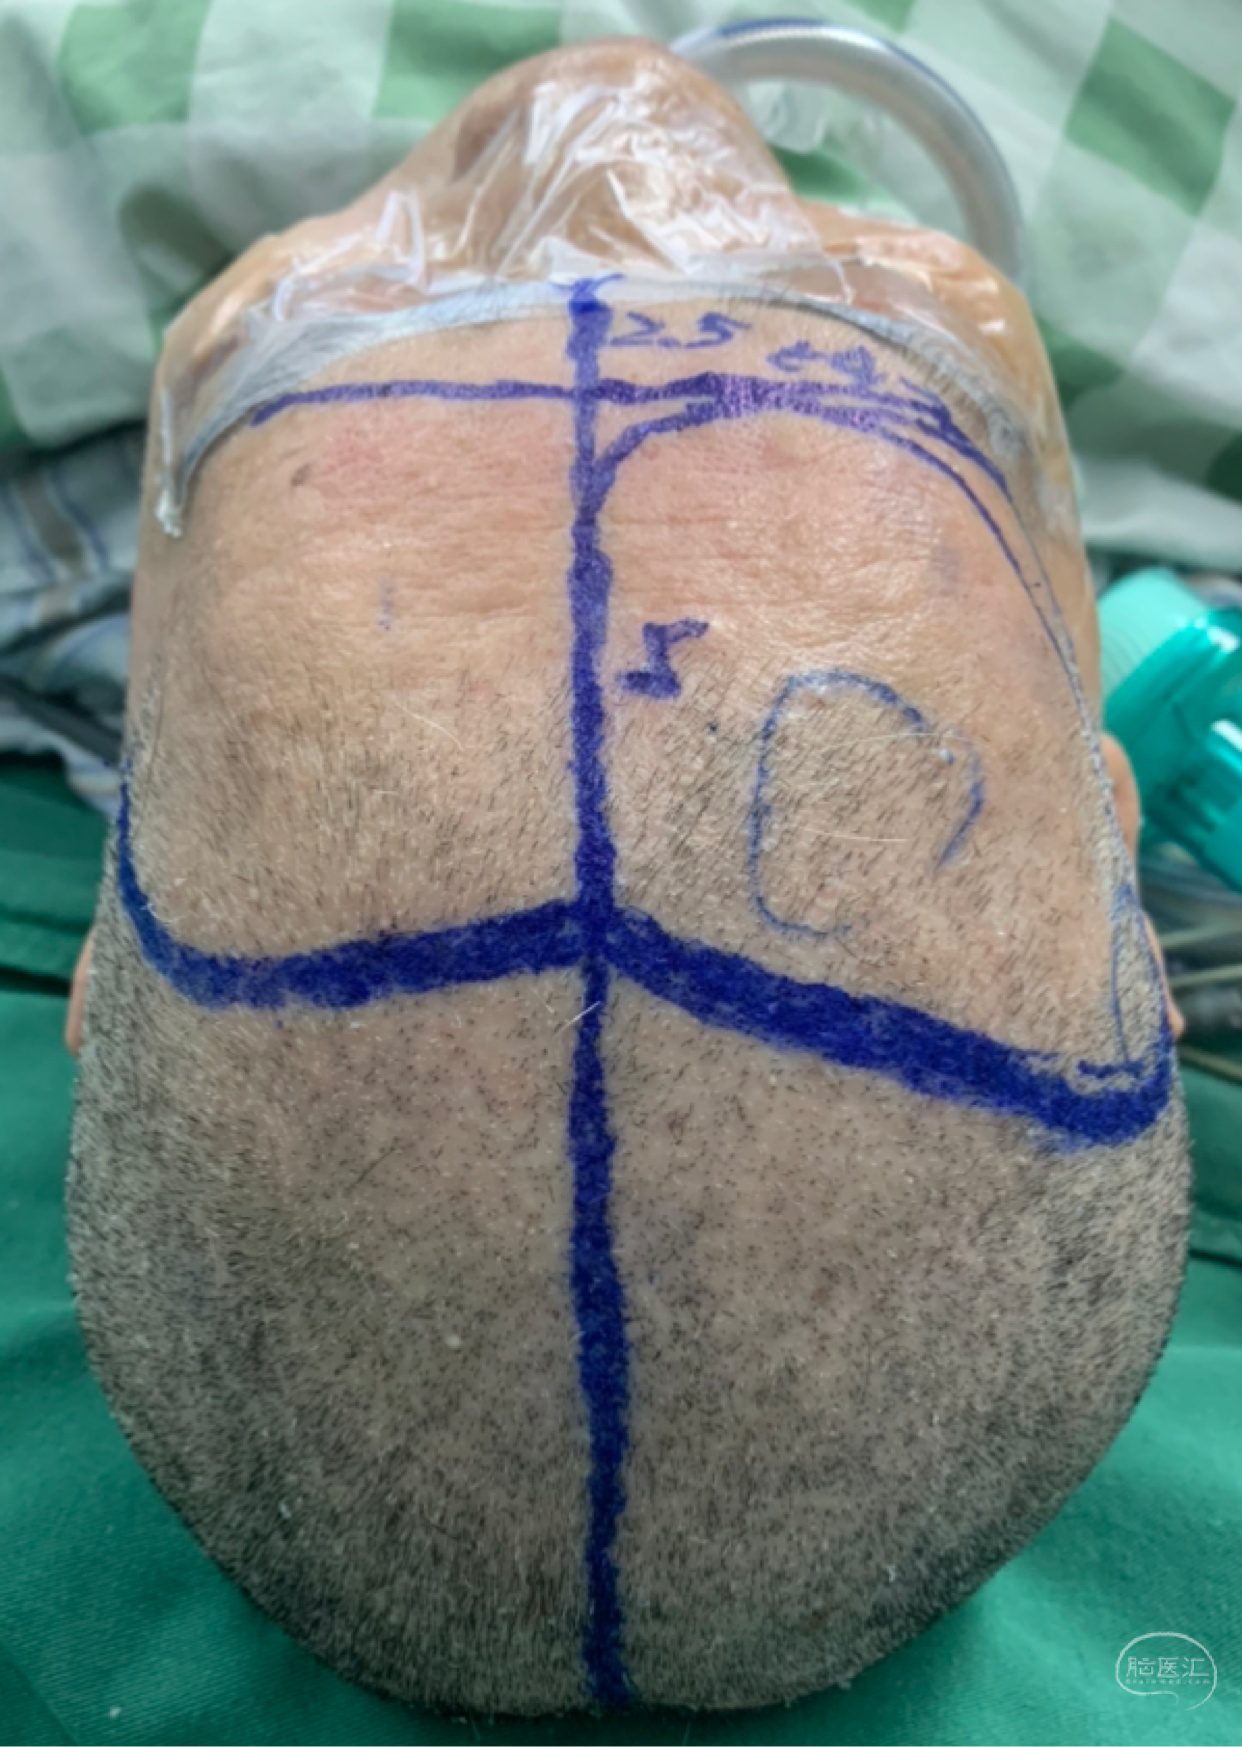

双侧入路计划(为降低优势半球损伤风险先右侧处理,实在不好搞再左侧)

从右额分块切除处理大部分后,因条件所限单侧入路风险高遂加开左侧额外侧(骨窗较右侧小)。